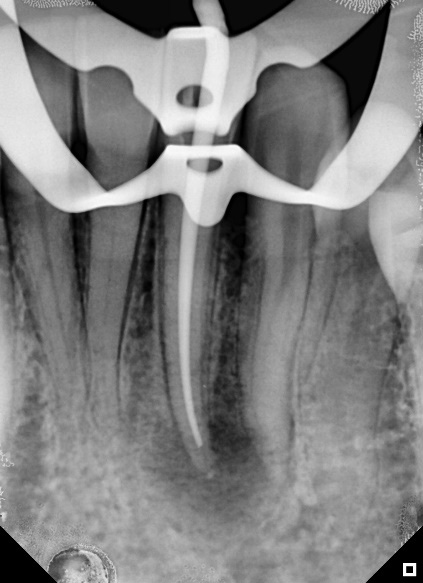

The first session involved anesthesia, endodontic access correction, absolute isolation, and root canal preparation. During the mechanical chemical preparation, constant irrigation and patency of the canal were used at each file change. The first session concluded with the canal being filled with the intracanal dressing BIO-C® TEMP® (Angelus), followed by a radiograph to confirm that the canal had been filled (Figure 2).

Figure 2: BIO-C® Temp medication applied to the canal after the preparation had been completely carried out